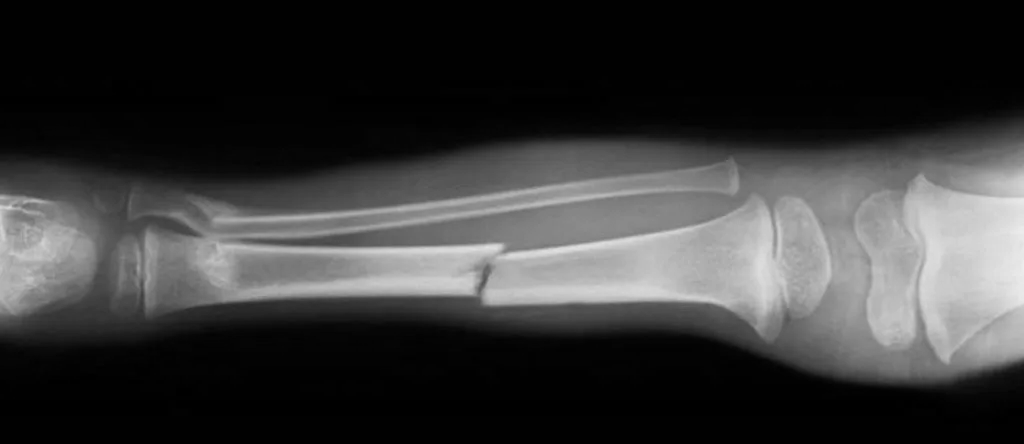

Основная сложность была в риске формального подхода со стороны членов ВВК. Они видят сотни людей и могут «обобщи» диагноз, не вдаваясь в детали пареза и трофических расстройств. Мы преодолели это за счет максимально полного пакета медицинских доказательств: результаты электромиографии (ЭМГ), снимки, подробные описания неврологического дефицита. Вторая сложность — необходимость подтверждения категории в вышестоящей комиссии. Мы заложили на это время и готовились изначально, что позволило пройти процедуру без задержек.

• Основной диагноз: Посттравматическая левосторонняя плечевая плексопатия... с глубоким парезом кисти... вследствие минно-взрывной травмы... с прямым указанием: «военная травма. Статья 27 пункт "б"».